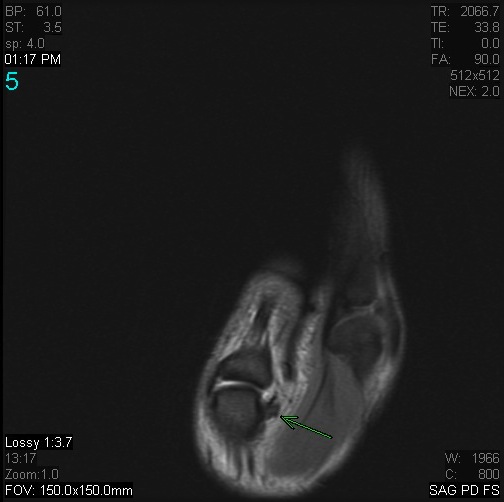

Figure 1 for case Stener lesion

Figure 1